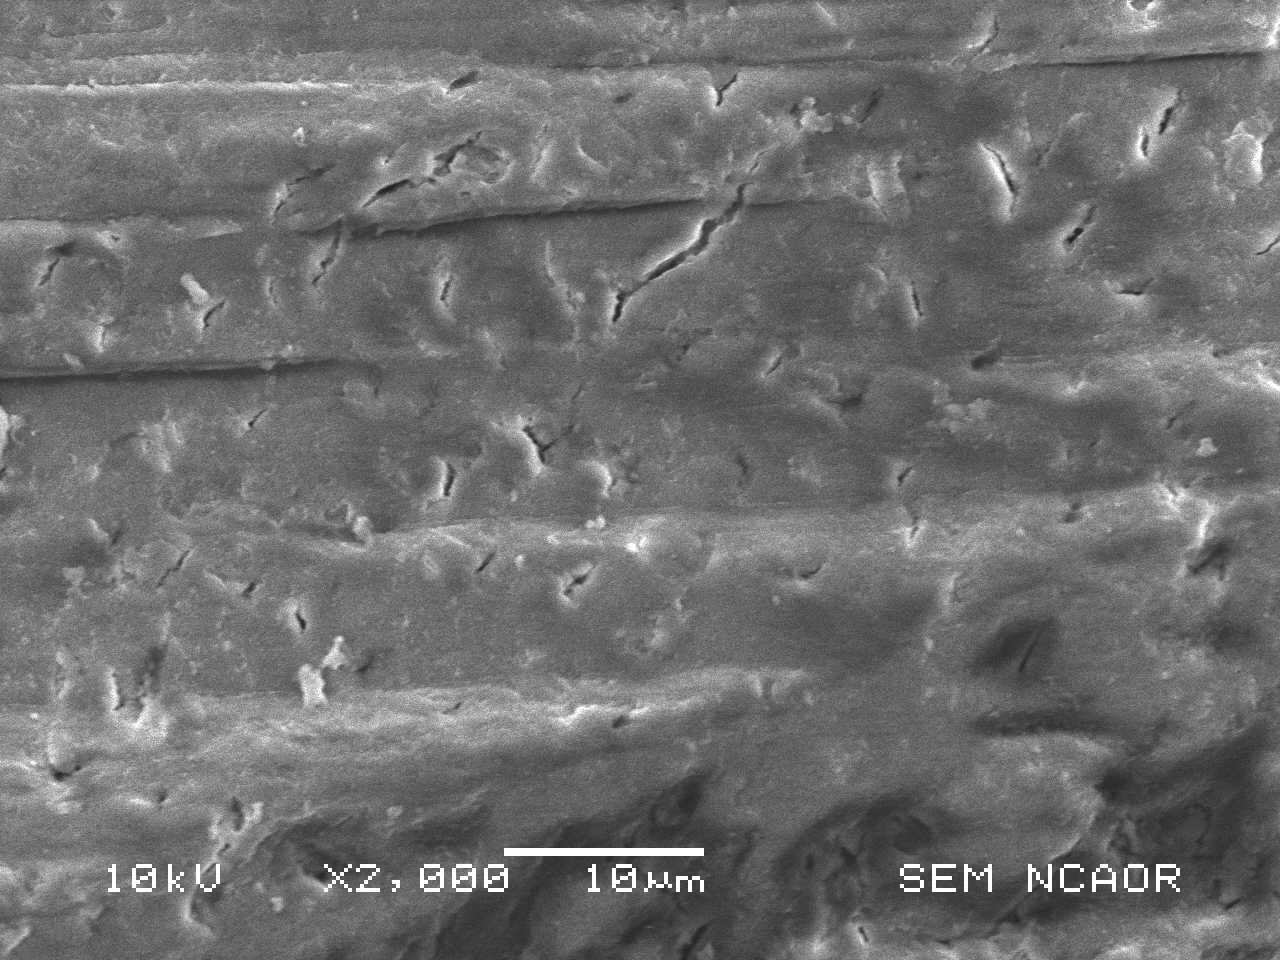

These sections were then observed under a scanning electron-microscope and occlusion of dentinal tubules was studied [Table/Fig-4 and 5].

Scanning electron microscope views of a section in Carbamide peroxide and NovaMin group showing occluded tubules

Tubule counting was performed on all SEM (Scanning Electron Microscope) images that were obtained at 2000X and 10KV. Three people separately examined each image and counted the number of completely blocked tubules, open tubules and partially occluded tubules.

Tubules that could not be fully visualized on the SEM images were not counted.

For each SEM image, the tubule counts from the three people were averaged together to obtain the number of open, partially occluded, and total visible (open + partially occluded) tubules. This method was followed by Anora Burwell [5] [Table/Fig-4].